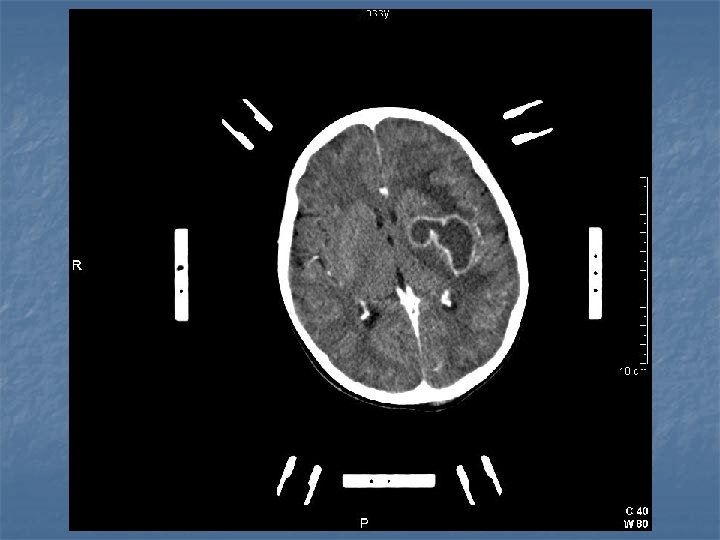

VII. Beyin absesi n n n Septik mikrovasküler yaralanma Fokal enfeksiyon “Serebrit” (septik parenkimal nekroz) Abse formasyonu

KİBAS LP KONTRENDİKEDİR! Tedavi: Abse ponksiyonu + Antibiyotik